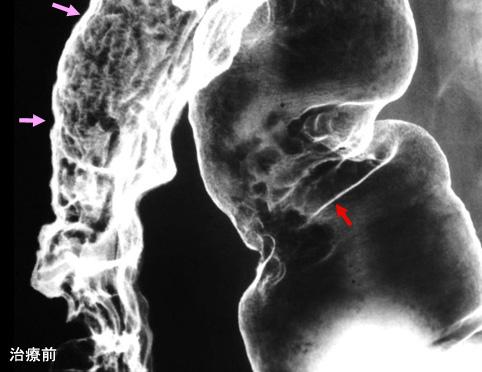

症例提示(所在地,施設名等): 佐賀県・ 佐賀県立病院好生館 (下田悠一郎先生からの提供症例)

疾患(病理主体)の分類炎症性・潰瘍性疾患/結核

部位(臓器別)大腸/2区域以上の大腸にまたがるもの

検査方法X-P